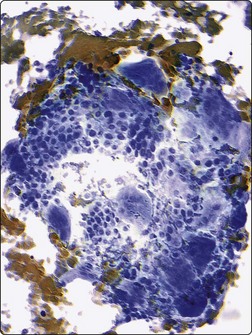

image

Fig. 17.2 Neuroblastoma

Cluster of cells arranged in a Homer-Wright rosette containing central neuropil. The presence of neuropil is the most helpful cytologic feature for rendering a definitive diagnosis of neuroblastoma (Diff-Quik, ×400).